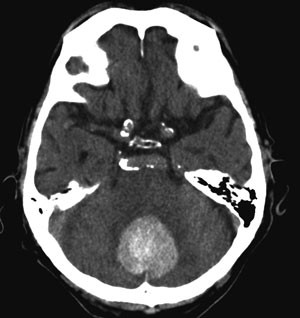

CT caput

Til tross for at infarkt og blødning fremtrer forskjellig, er det ikke mulig å skille disse to tilstandene fra hverandre med sikkerhet uten bildediagnostikk. CT caput er det primære valg og bør utføres umiddelbart etter hospitalisering. Videre er det ofte uklart om det dreier seg om en spontan eller en traumatisk blødning, eksempelvis etter fall. CT gir informasjon om lokalisasjon og omfang av blødningen, om det er intraventrikulært blod og dermed fare for utvikling av hydrocephalus eller om det er fare for herniering under falx eller gjennom tentorialåpningen. CT med kontrast og nøyaktig samme snittføring som uten kontrast, gjerne supplert med CT-angiografi, kan gi informasjon om blødningskilde som arteriovenøs malformasjon eller aneurisme, og bør utføres på vid indikasjon.

Tidligere trodde man at intracerebral blødning var en øyeblikksbegivenhet der blødningen fant sted i løpet av minutter og nesten umiddelbart stoppet grunnet koagulasjon og mottrykk fra omgivende hjernevev. Vi vet nå at bortimot 40 % av hematomene der den første CT-undersøkelsen utføres innen tre timer etter symptomdebut ekspanderer i løpet av de første timene (17) (fig 2). Antakelig skyldes dette en kombinasjon av fortsatt blødning fra det rumperte kar og mekanisk skade av omgivende kar, noe som fører til blødninger også fra disse (20). CT-angiografi viser at kontrast akkumuleres ekstravasalt i hematomet hos nesten halvparten av dem som undersøkes innen seks timer etter symptomdebut. Slik lekkasje er assosiert med økt vekst av hematomet og økt dødelighet (21). Erkjennelsen av at blødningen ofte fortsetter i flere timer etter debuten kan ha stor betydning for moderne behandling av hjerneblødning.

Intracerebral blødning er en alvorlig tilstand – 35 – 50 % av pasientene dør i løpet av den første måneden, halvparten av disse i løpet av de første to døgn (24). Etter et halvt år er bare ca. 20 % blitt så bra at de er uavhengige av hjelp fra andre (24). De viktigste prediktive faktorer for tidlig død er redusert bevissthetsnivå og stort volum på blødningen. I en pasientserie døde over 90 % av dem med Glasgow Coma Scale (GCS) < 9 og blødningsvolum > 60 ml innen en måned, mot 17 % av dem med GCS > 8 og < 30 ml blod (25). Blødningens volum kan estimeres ved formelen A x B x C dividert med 2, der A er blødningens største diameter, B er diameteren vinkelrett på A og C er antall snitt med synlig blod multiplisert med snittykkelse (25).

Nytten av kirurgisk evakuering av supratentorielle hematomer er omstridt. Randomiserte studier med kraniotomi versus beste medisinske behandling har ikke vist gevinst av kirurgisk intervensjon (33). I ikke-randomiserte pasientserier er det som regel heller ikke vist nytte av kirurgi. Stuporøse eller komatøse pasienter kan i enkelte situasjoner opereres på vital indikasjon, selv om hovedregelen er at man avstår fra kirurgi ved alvorlig bevissthetsreduksjon – GCS < 5. Små hematomer (< 10 ml) eller hematomer med minimale nevrologiske utfall ekspekteres. Tidlig kirurgisk evakuering av hematom, innen fire timer etter debut, kan innebære økt dødelighet grunnet tidlig reblødning (34). Kirurgisk evakuering anbefales derimot ved cerebellar blødning, grunnet faren for trykk mot vitale strukturer i hjernestammen, noe som kan ha fatale konsekvenser (fig 3), ved blødning med assosiert arteriovenøs malformasjon eller aneurisme, som bør behandles for å forebygge nye blødninger, og kanskje hos unge pasienter med moderat eller stor lobær blødning og tegn til klinisk forverring (19).